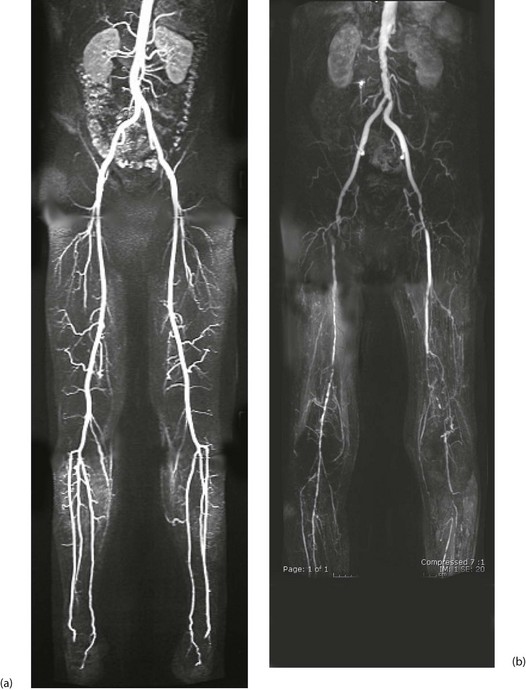

Arteriography (see Ch. 5): Arteriography should be reserved for patients thought to require angioplasty or reconstructive surgery. It maps the arterial system (see Fig. 41.1), showing sites and severity of stenoses and occlusions, the quality of inflow (arteries feeding the area of concern) and the runoff (arteries beyond the main obstruction, see Fig. 41.2). Arteriography is sometimes used wrongly by non-specialists to assess chronic arterial insufficiency but it cannot measure blood flow to the tissues or dynamic circulatory responses to exercise; it helps only with the mechanics of revascularisation. Traditional arteriography is performed via direct arterial puncture but carries risks of vessel trauma and high doses of contrast aggravating chronic renal impairment. It is being replaced by less invasive CT and MR angiography which use lower doses of intravenous contrast media.

Fig. 41.2 Arteriograms comparing the normal with typical patterns of arterial obstruction affecting the lower limbs

(a) This magnetic resonance angiogram is entirely normal, showing smooth, regular arterial walls, all branches intact and three normal infra-inguinal arteries below knee on each side. (b) This composite subtraction arteriogram was performed because the patient suffered bilateral severe claudication. The aorta is irregular and narrowed by atherosclerosis from above the renal arteries to the bifurcation. The common, internal and proximal external iliacs are normal and smooth but the right external iliac is occluded and the left stenosed. Both profunda femoris arteries are occluded. The superficial femoral arteries are both diseased and occluded distally. On the left side, collaterals are visible around the knee area. The infrageniculate vessels are diseased on both sides with stenoses and occlusions. Reconstruction would have been extensive, difficult and risky, and hence conservative management alone was undertaken, in the absence of rest pain or tissue loss